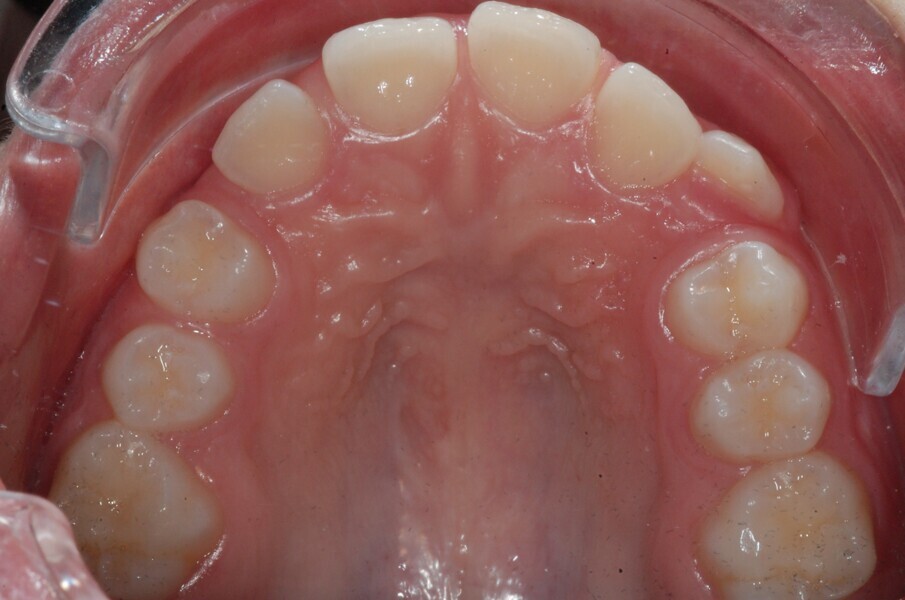

A 14-year-old female patient presented with the chief complaint of midline deviation and dental crowding in both arches. Facial analysis showed a hypodivergent growth pattern, a normal nasolabial angle, a harmonious profile and proper chin projection. Clinical examination revealed a Class III skeletal relationship (ANB = 0°) and Class I molar relationship. The maxillary right canine was absent, and this had led to space loss and mesial drift of posterior teeth on the right side, resulting in a slight Class II molar relationship. The maxillary left canine had erupted in a high position. The mandibular arch displayed crowding despite the agenesis of the right second premolar and the persistence of the primary molar (Figs. 3–11). The radiograph showed the probably premature loss of the maxillary right primary canine and consequently impacted maxillary right permanent canine, and the agenesis of the mandibular right second premolar and the mandibular right third molar (Fig. 12).

Fig. 3